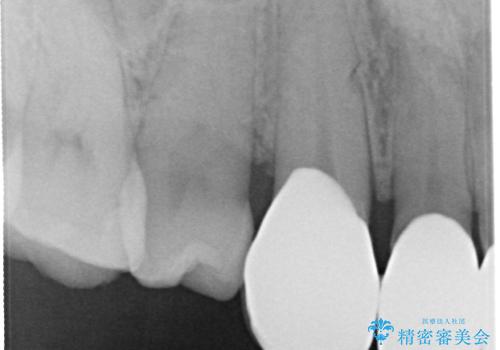

以前に装着されていたものは全て連結されており、清掃性があまり良くありませんでした。

一つ一つを独立したかぶせ物を装着することで、フロスも可能になり、清掃性が向上しました。